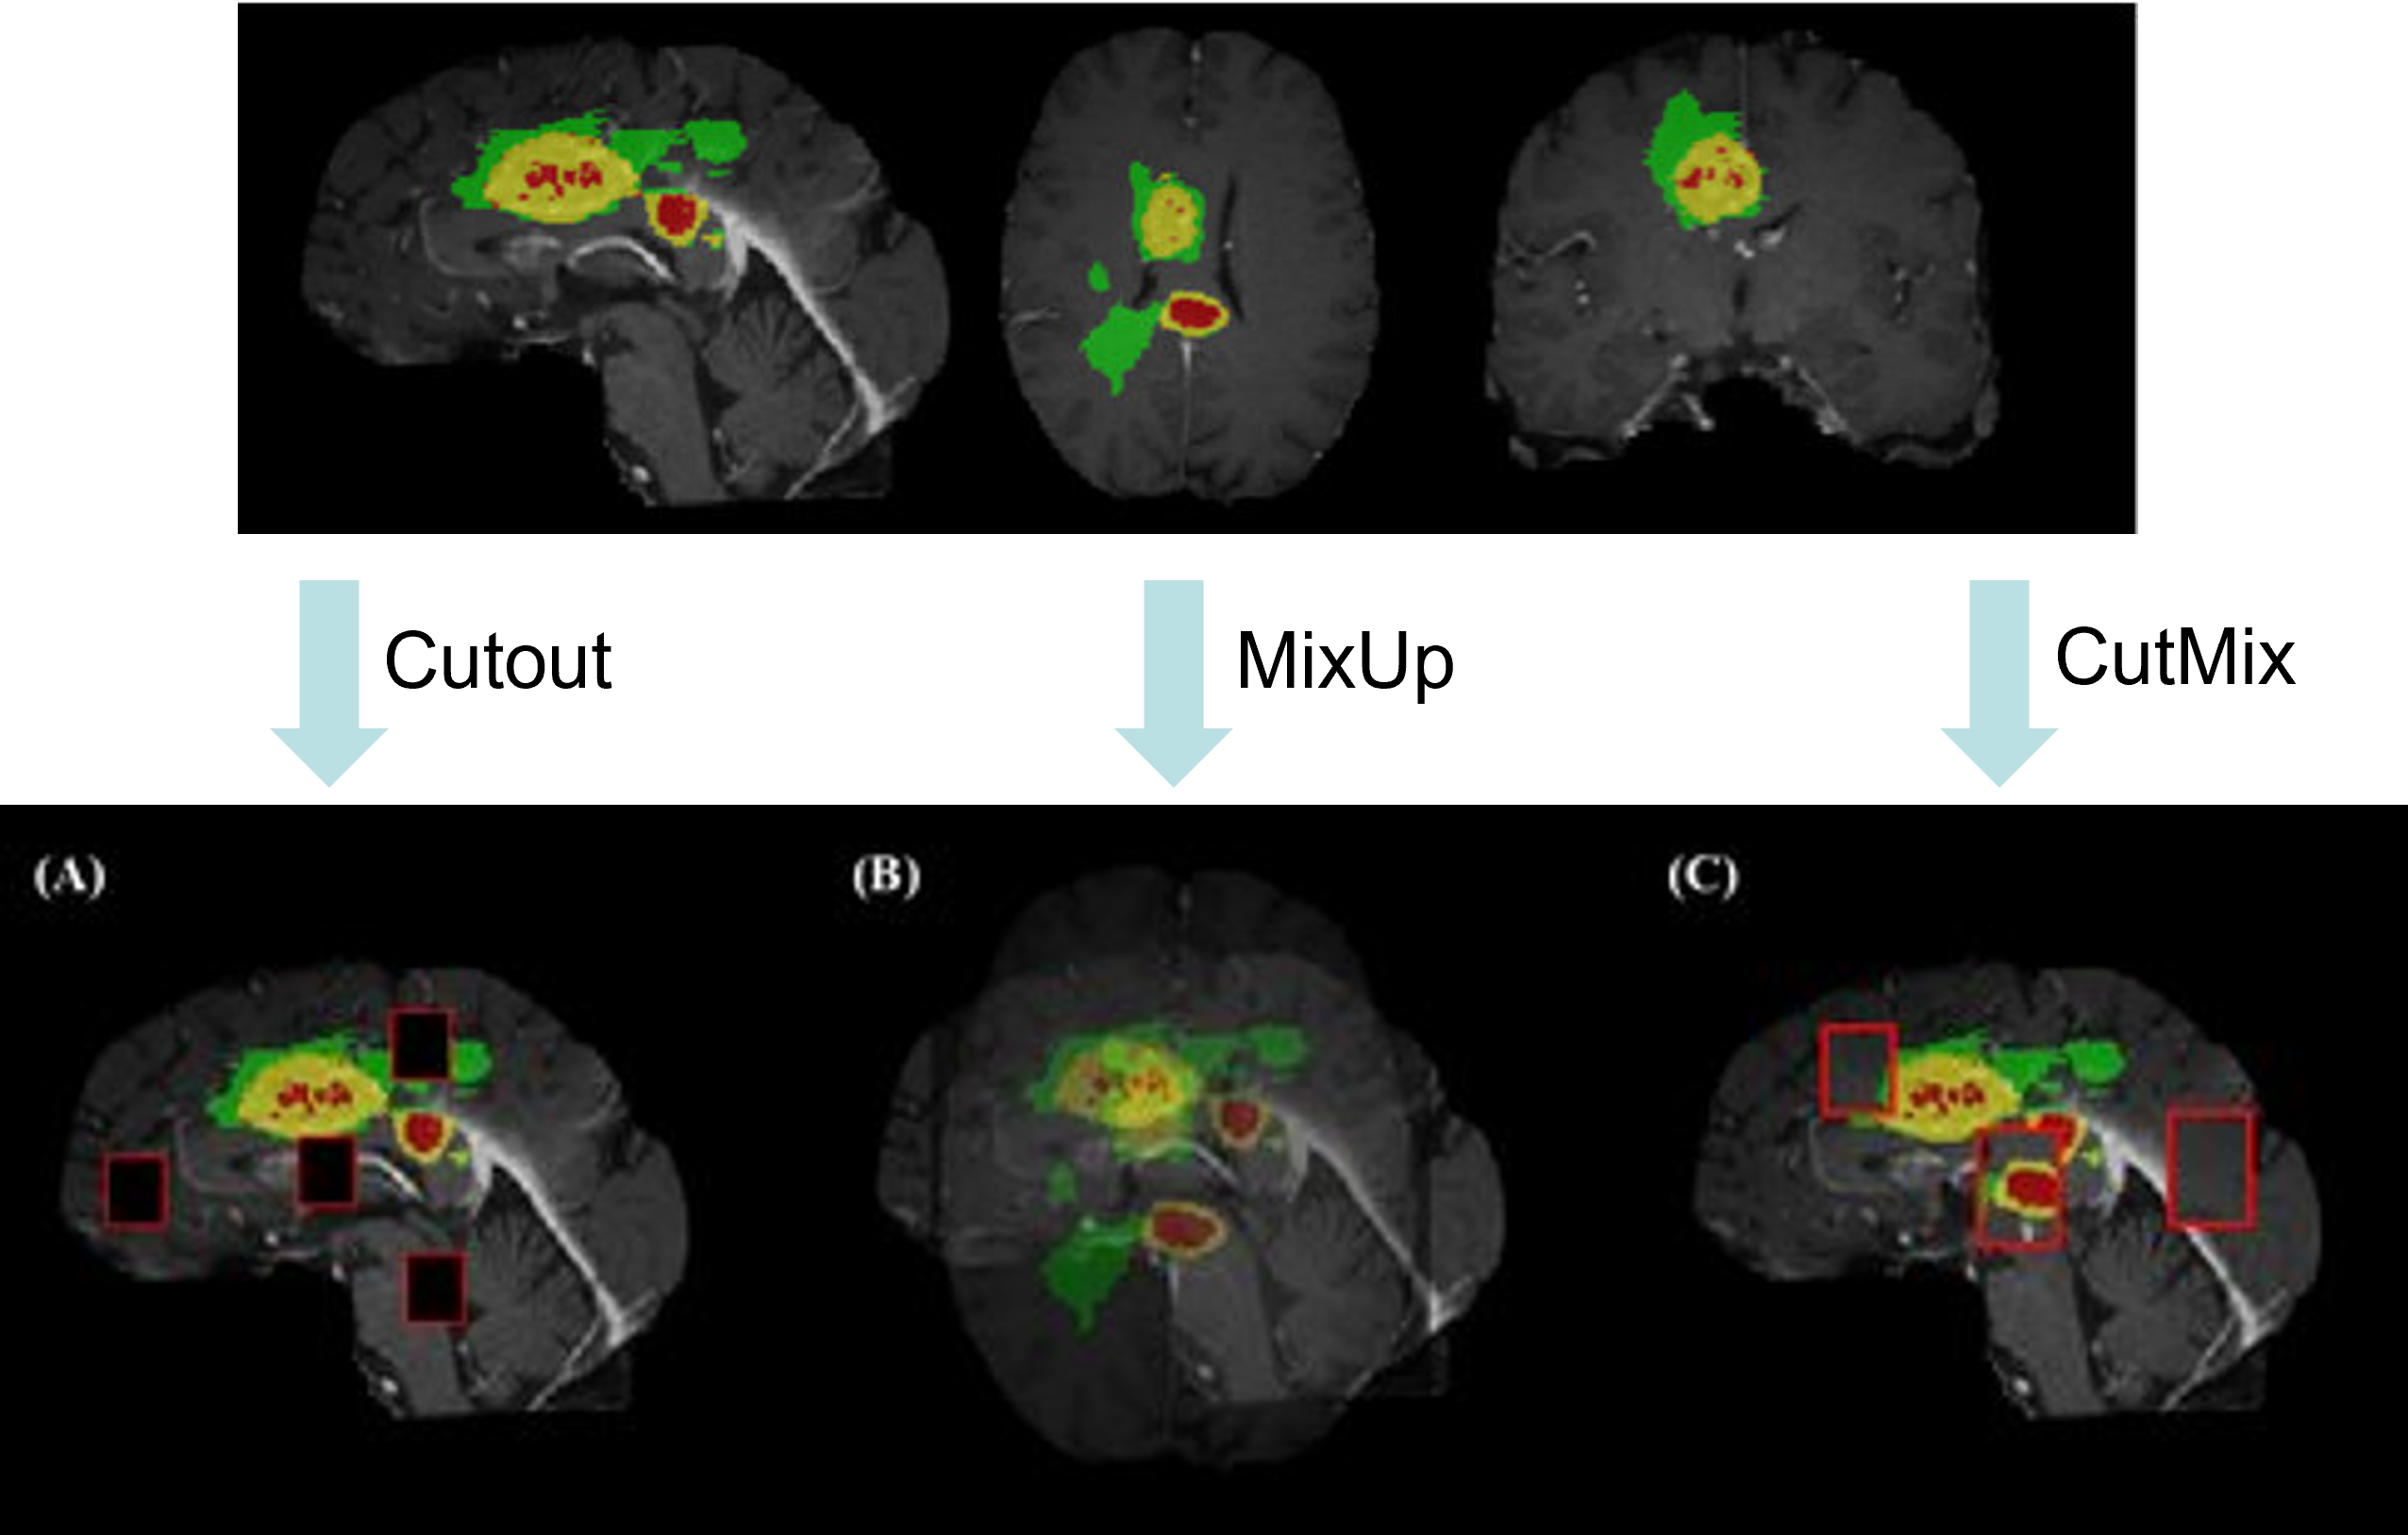

1. Cutout

This augmentation method consists in randomly masking out square regions of input during training. [11] [16]

2. MixUp

This augmentation approach takes the input of two different images and mixes them to give back the output of an interpolation of the images and the labels. [5]

It produces virtual feature-target vectors (x = λx_i + (1 −λ)x_j, y = λy_i + (1 −λ)y_j), starting from (x_i, y_i) and (x_j, y_j) which are two feature-target vectors from the training data, and λ \in [0, 1]. [4]

3. CutMix

For this approach, the input consists also of two images. A patch is cut from the first image and pasted on the second one. Proportionally to the area of the patches, the labels are also mixed [5]

The input is observed as x ∈ R^{W×H×C} for the training image and y for its label, respectively. CutMix generates a sample (\tilde x, \tilde y) by combining two training samples (x_A, y_A) and (x_B, y_B) . The generated training sample (\tilde x, \tilde y)is used to train the model. The combining operation is defined as:

| \tilde x =M \odot x_A + (1−M) \odot x_B \newline \tilde y = λy_A + (1 −λ)y_B, |

where M ∈ \{0, 1\}^{W×H} is a binary mask indicating where the cutting and pasting takes place. [5]